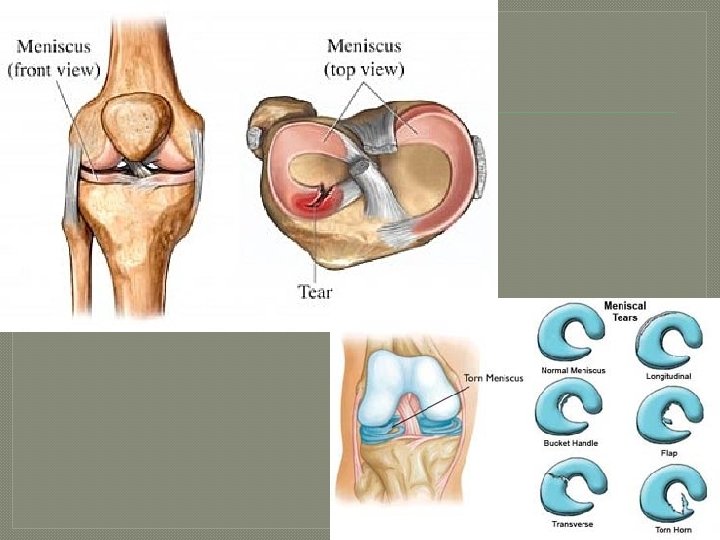

Knee Anatomy – Soft Tissues Menisci of the knee • Lateral Meniscus – Joint cartilage that deepens the knee joint. • Medial Meniscus – Joint cartilage that deepens the knee joint. Has a deep attachment to the MCL. • Outer 1/3 has a blood supply, rest is avascular.

Meniscus Tear Common Injuries Mechanism of Injury Weight bearing with rotational force. Signs and Symptoms Swelling, joint line pain, loss of motion, locking or giving way. Treatment RICE Avascular area: Surgically trimmed and smoothed. Vascular area: Surgically repaired. Prevention Strategies Lower extremity strengthening and conditioning.